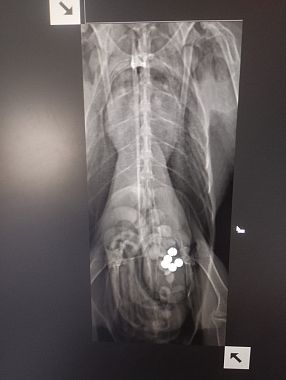

LIVORNO — Un'Avocetta con lo stomaco pieno di piombo e intossicata dal metallo è stata soccorsa lunedì scorso in un giardino privato e ricoverata al Centro Cruma di Livorno gestito dalla Lipu.

"Se le condizioni lo permetteranno, nei prossimi giorni verrà effettuata anche una lavanda gastrica per rimuovere direttamente i pallini ancora presenti nello stomaco. In alternativa - spiega una nota - si spera che l’animale riesca a espellerli naturalmente, evitando un’ulteriore assimilazione del metallo".